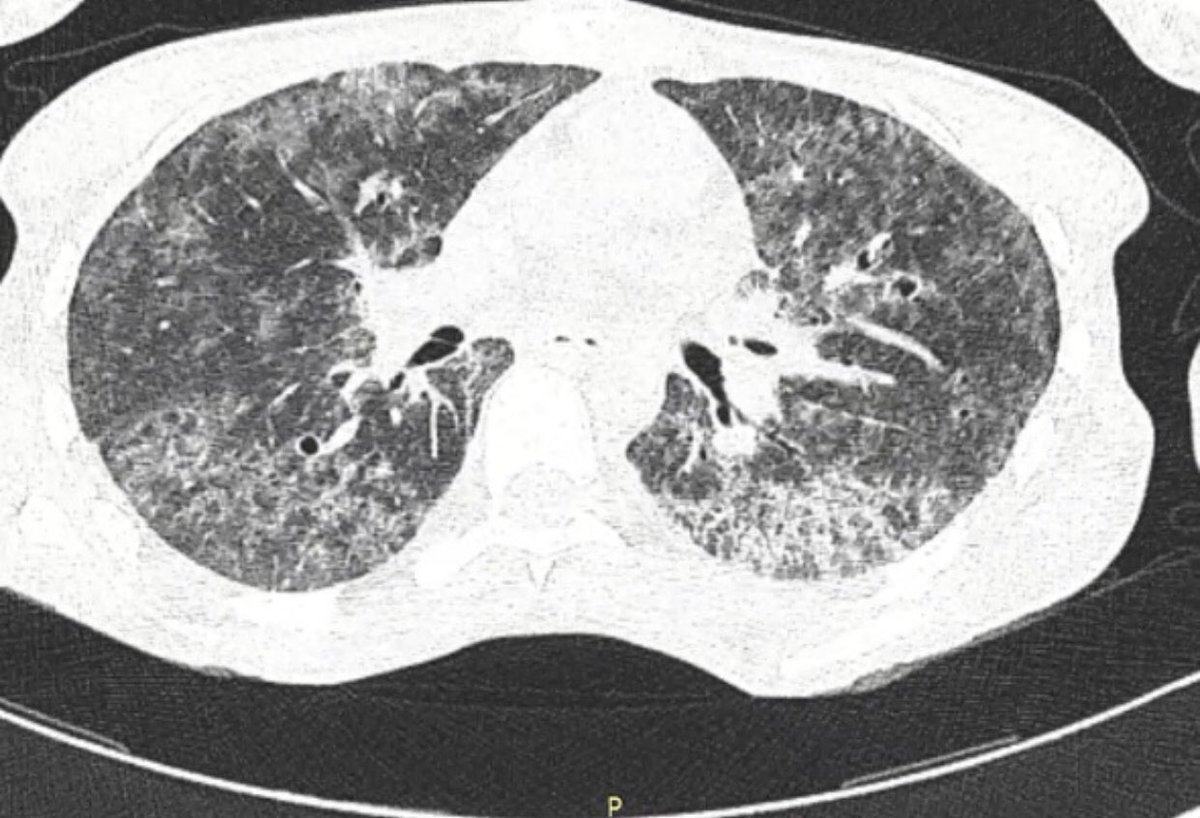

Jigsaw puzzling in the ICU: diagnosing invasive pulmonary aspergillosis.

@drjordirello@PneumoINSPIRE@VVIZV1#fungus#aspergillus#ICU#aspergillosis@JMellinghoff@marta_bork@WendyChaboyer@RKleinpell@BronaghBelfast@drbencb https://www.ncbi.nlm.nih.gov/pubmed/31361683 pic.twitter.com/lAynu8h3E6